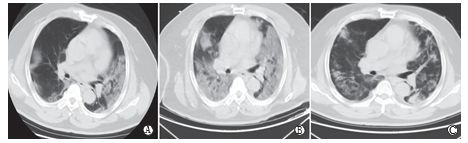

(2)双肺多发、斑片状或大片状实变,并少许网格样或蜂窝状小叶间隔增厚,以中下叶为著(图3,26例,31.3%,共计83例),老年人或重症患者多见。

图3 典型CT/X线影像表现(例3)

男性,65岁,发热4 d(38.7℃)。实验室检查,WBC:3.72×109/L(正常),LYMPH:0.90×109/L(减低),CRP:53.0 mg/L(升高), PCT:0.10 ng/ml(升高),肝功能减低,低蛋白血症,轻度贫血。A、B示右肺中叶大片实变和下叶后基底段斑片状实变、内见充气支气管征,3C示左肺下叶外基底段斑片状实变,右侧胸腔少量积液。